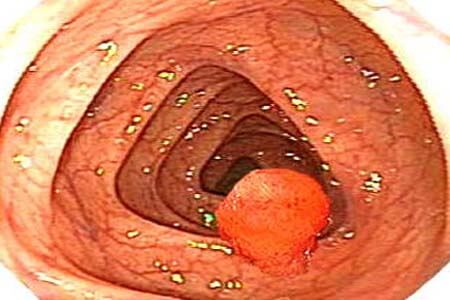

Hình ảnh nội soi polyp nằm sâu trong ống hậu môn

Ở giai đoạn khởi phát, khối polyp thường nằm sâu bên trong, mắt thường không thể nhìn thấy. Qua hình ảnh nội soi chuyên dụng, bạn sẽ thấy:

- Khối u nhú màu hồng nhạt hoặc đỏ sẫm, bề mặt thường trơn láng nhưng dễ bị trợt xước.

- Nếu là polyp ác tính, hình ảnh nội soi có thể cho thấy các mạch máu tăng sinh bất thường hoặc bề mặt sần sùi như bông cải.

- Polyp có cuống: Hình ảnh giống như một quả anh đào hoặc cây nấm nhỏ, gắn với thành hậu môn bằng một sợi dây mô (cuống). Loại này rất dễ di động mỗi khi có áp lực từ việc đại tiện.